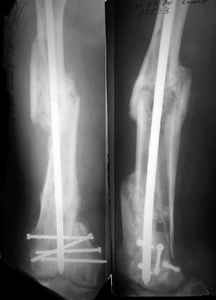

Attached are few examples from our Hospital:

A. Difficult reductions, even in retrograde nailing (my preference, easier control of "small" distal fragment) and it is much, much harder to do it anterograde (Alex, do you have one good case in your collection of anterograde nailing in very distal fractures - as you have suggested that I

should have done it in my previously posted case?

Malpositioning is much too common (recurvatum, varus - valgus).

B. Fixation loosening: distal cutting of the nail, non-unions do happen (cases attached).

Locking Plating has more distal screws than any nail, fixed angles and provides much better fixation, especially in osteoporotic bone.